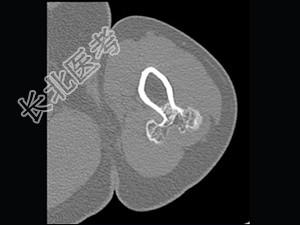

单项选择题男,28岁, 左手臂上部可扪及一硬结,有轻压痛, 结合图像,最可能的诊断是 ( )

A、骨软骨瘤

B、骨旁骨瘤

C、表面骨肉瘤

D、皮质旁软骨瘤

E、皮质旁软骨肉瘤